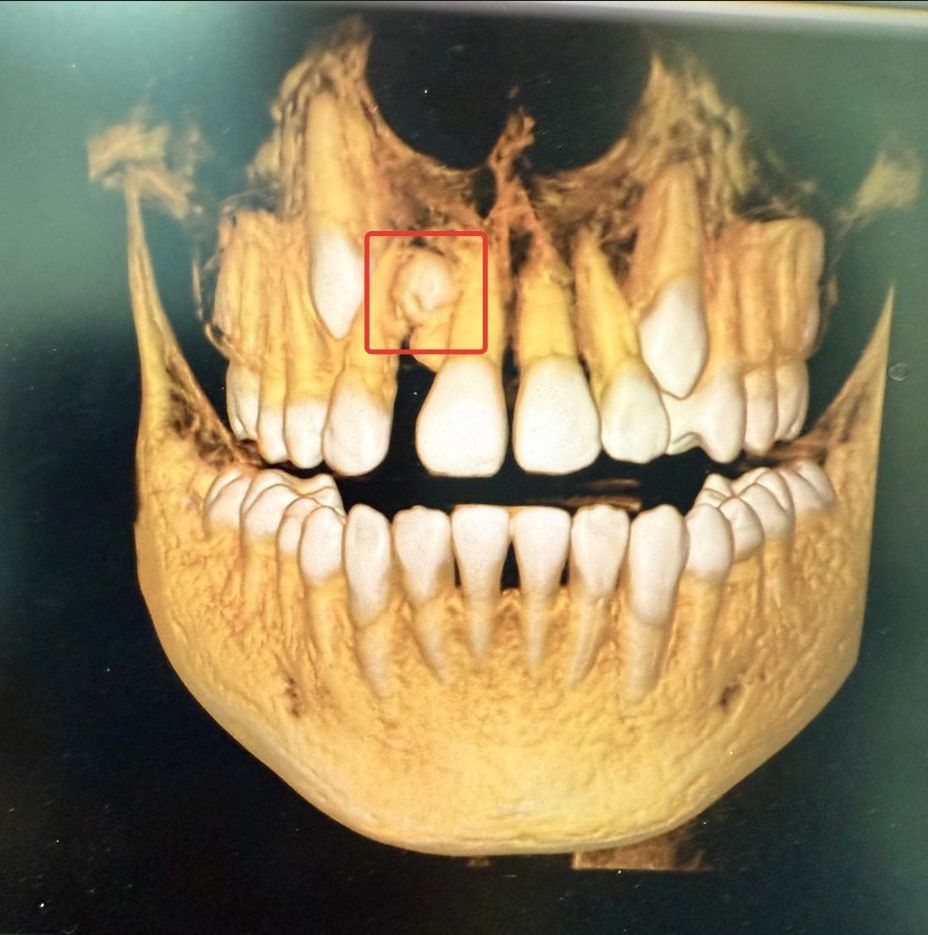

Мальчик обратился к ортодонту с жалобами на эстетические проблемы. При проведении компьютерной томографии был обнаружен сверхкомплектный зуб на верхней челюсти, расположенный между центральным и боковым резцом. Сверхкомплектные зубы — это аномалия, при которой у человека появляется больше зубов, чем обычно. Она может проявляться как у детей с молочными, так и у взрослых с постоянными зубами.